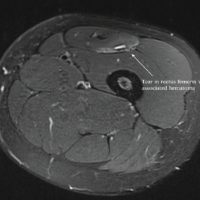

After discussing treatment options, including revision fixation, osteotomy, and arthroplasty, and given the chronic nature of the injury and degenerative articular changes, the decision was made to proceed with TKA. The procedure was performed under spinal anesthesia with full aseptic and antiseptic precautions. After painting and draping, a standard medial parapatellar incision was made. Bone cuts were taken as per protocol. Intraoperative findings revealed a fibrous non-union with articular surface damage (Fig. 4 & 5). The medial condyle non-union was exposed, debrided, and fixed using a Heibat screw for stable internal fixation.

The patient was monitored in the post-operative unit and began physiotherapy and mobilization with partial weight-bearing on the 2nd post-operative day. Wound healing was satisfactory, and the patient was mobilized on day 2 with partial weight-bearing using a walker. Physiotherapy was continued to regain ROM and muscle strength. Gradual weight-bearing began after 3 weeks. At the 6-week follow-up, the patient reported significant pain relief and improved ROM (0°–100°). At the 3-month follow-up, he resumed independent ambulation without support. Post-operative radiograph showed well-aligned total knee prosthesis with condylar screw fixation (Fig. 6) and no signs of loosening or infection. Radiographs confirmed healing of the fracture and osteochondral plugs.